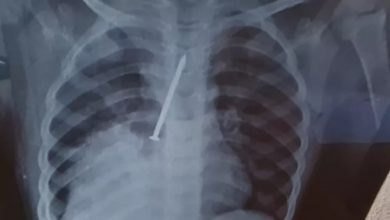

Cremeb-BA anuncia apuração sobre conduta dos profissionais que atenderam criança que morreu com prego no pulmão

O Conselho Regional de Medicina do Estado da Bahia (Cremeb) informou que vai investigar possíveis responsabilidades dos médicos que atenderam…